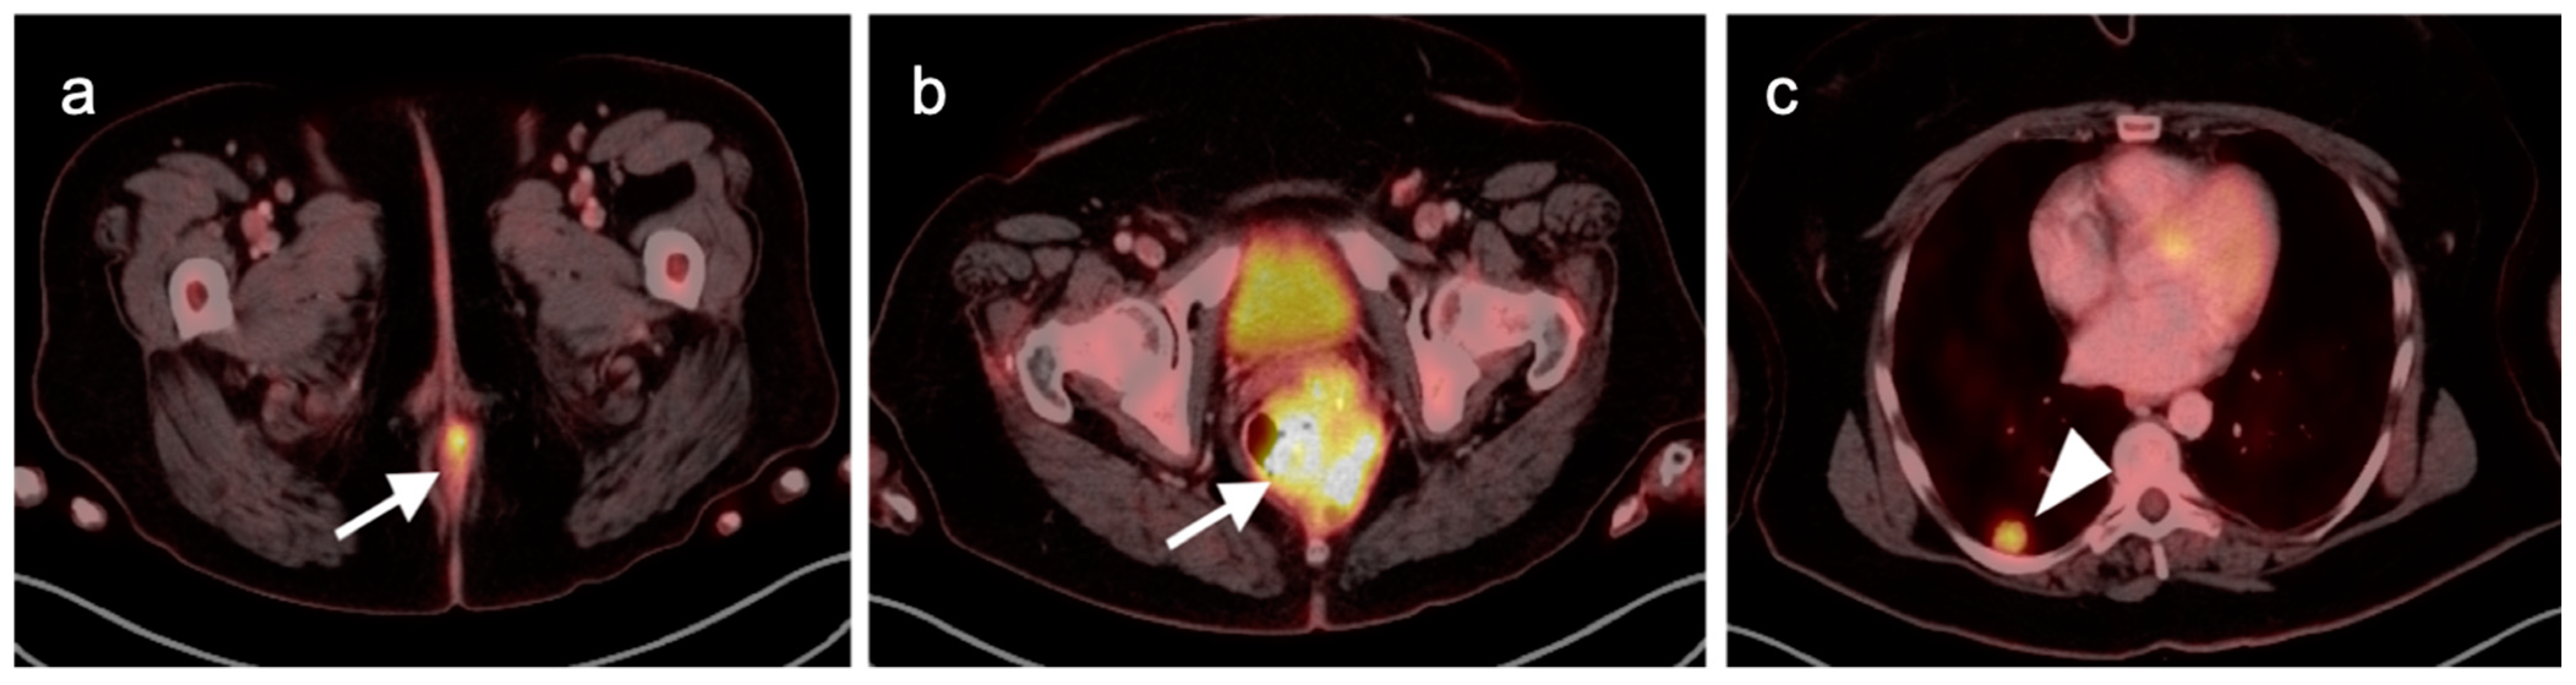

10. Anal Carcinoma